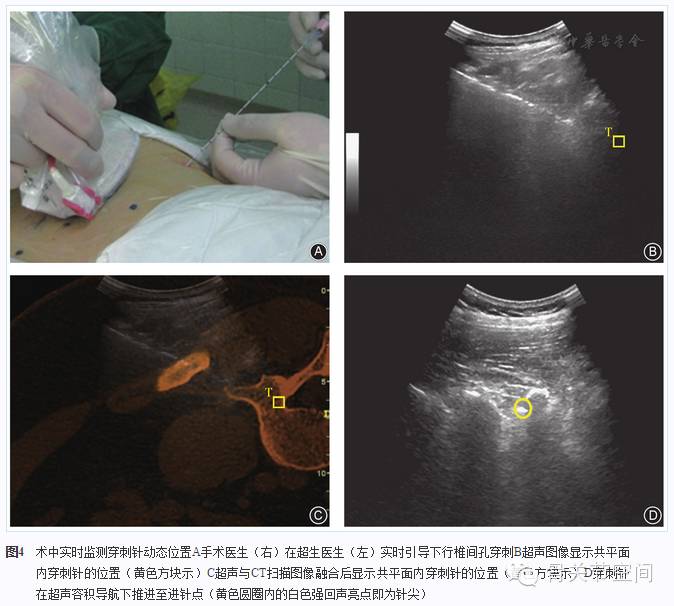

2.超声容积导航引导下椎间孔穿刺

图像融合后,需确保电磁追踪器及患者的相对位置不变。消毒铺单,以腹腔镜消毒隔离套包裹探头,实时引导穿刺。右屏矢状位CT图像上锁定病变节段椎间孔最下缘为进针点,左屏超声图像中同步实时显示该点,准确寻找并锁定(图3)。旋转探头至横切位,调整至靶点区方框尽可能小或为"十"字时确定为进针点。应用超声仪导航实时引导穿刺针在病变节段行平面内穿刺(图4)。